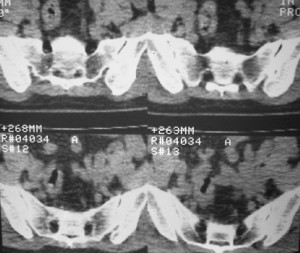

标题: CT7246: F,30岁,下腰痛,同事的片子,请老师们看看,初 [打印本页]

标题: CT7246: F,30岁,下腰痛,同事的片子,请老师们看看,初

典型的致密性髂骨炎

典型的双侧骶髂关节致密性骨炎.

何谓髂骨致密性骨炎?髂骨致密性骨炎是发生于髂骨耳状关节部分的骨质密度增高性疾病。病因迄今不明,可能与妊娠、机械性劳损、病灶性炎症有关。本病好发于20~35岁的育龄妇女,偶见男性。

髂骨致密性骨炎的临床表现与体征:腰骶部疼痛,多呈慢性、间歇性酸痛、隐痛,可向一侧或双侧臀部及大腿后侧扩散,但不沿坐骨神经方向放射,步行、站立、负重及劳累后加重,咳嗽、打喷嚏不能使疼痛明显加重,休息后症状减轻。患者腰骶角加大,局部有压痛和肌紧张,骨盆分离和挤压试验阳性,“4”字试验阳性,化验检查多在正常范围内。x线检查,骶髂关节间隙整齐清晰,靠近骶髂关节面中的髂骨耳状关节部分骨质密度增高,呈均匀浓白边缘清晰的骨质致密带,骨小梁消失,无骨质破坏。本病应注意与早期强直性脊柱炎、骶髂关节结核相鉴别。